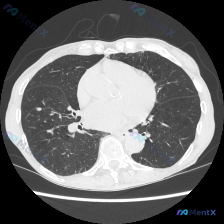

看到一份胸部CT肺窗的影像资料,整理了一下分析思路,和大家交流讨论。 病例资料 影像类型:胸部CT肺窗横断面图像 主诉:仅提供影像学资料,无临床症状及病史信息 影像学分析 解剖结构观察 - 肺实质:右肺上叶可见一枚类圆形高密度结节影,边界相对清晰,周围肺组织未见明显渗出或实变。双肺肺野透亮度均匀,无...

看到一个胸部CT肺窗的病例资料,整理了一下思路,和大家分享讨论。 病例资料 - 主诉/现病史:无具体描述 - 胸部CT肺窗表现: - 图像质量良好,无明显伪影 - 右肺中外带可见一个类圆形实性结节,边界较清晰,密度均匀 - 左肺野未见明显结节或实变影 - 气管及双侧主支气管开口通畅 - 肺门血管结构...

看到一个胸部CT病例资料,整理了一下思路,想和大家讨论。 病例信息 影像学情况 - 检查类型:胸部CT肺窗横断面(主动脉弓下方层面,气管分叉前后区域) - 图像质量:清晰,无明显呼吸/运动伪影,对比度适中 - 问题提示:怀疑有结节 影像学分析要点 1. 整体结构:双肺野透亮度基本对称,无明显局限性密...